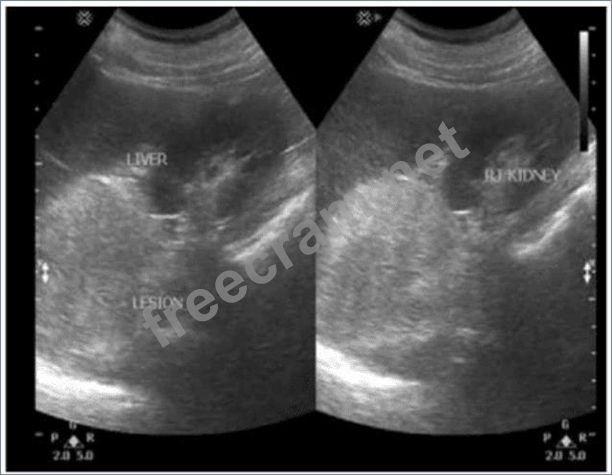

Which finding is most likely demonstrated in these images of a hypertensive patient with a history of hematuria?

Question 38: Which finding is most likely demonstrated in these images of...